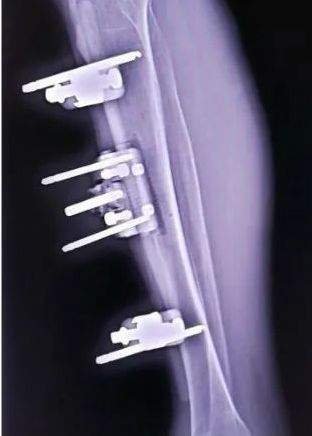

Ilizarov 技术横向骨搬移,是在患者右小腿部通过牵拉骨块,可以从胫骨骨髓腔内重新生成一套微血管系统,于末端微细血管融合,从而重新改善下肢血液循环,使因部分闭塞造成的缺血坏死组织趋于缓解直至痊愈。